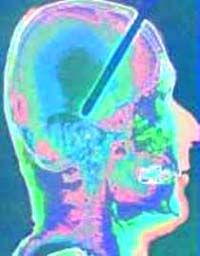

<<< Ein Mikrochip wird mit Nerven verbunden

Ein Mikrochip wird

mit Nerven verbunden

Auch in Deutschland laufen seit einiger Zeit Projekte, die eine Verbindung von Neurologie, Biochemie, Mikroelektronik und Computertechnik realisieren wollen. Eines davon findet sich in der Abteilung Membran- und Neurophysik am Max-Planck-Institut (MPI) für Biochemie in Martinsrid bei München. Laut Martin Jenker, Mitarbeiter in der Abteilung, wollen die Wissenschaftler dort verstehen, wie neuronale Netze arbeiten: "Wir nehmen keine großen Strukturen auseinander, um sie zu analysieren, sondern bauen winzige 'Hirne' unter genau definierten Bedingungen." Um das zu erreichen werden künstliche neuronale Netze auf Halbleiterchips kultiviert: Auf die ebene Chipoberfläche bringen die Münchner Forscher einzelne Nervenzellen von Ratten, Schnecken oder Blutegeln auf, die sich wieder zu einem Gewebe zusammenschließen. Um strukturiertes Wachstum auf der künstlichen Oberfläche zu erreichen, werden mit Hilfe von photolithographischen Methoden definierte Bahnen vorgegeben, auf denen die Zellkörper anfangen, ihre Fortsätze auszubilden. Als direkte Schnittstelle zwischen Nervenzellen und Computertechnologie dienen sogenannte Feldeffekttransistoren (FET). Mit diesen elementaren Bauteilen, die direkt unter der Chipoberfläche eingebaut sind, können die Forscher ohne Schädigung der Zellen deren Aktivität messen. Bei den Schnecken- und Blutegelzellen ist es mit Hilfe der Chips inzwischen sogar schon gelungen, künstlich Aktivität auszulösen.